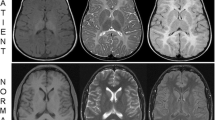

The unaffected III.5 has together with his cousin III.6 eight offspring, among them four fetuses with severe primary microcephaly diagnosed in the first trimester of pregnancy by ultrasound. All four affected fetuses presented with microcephaly and retrognathia already present at 15 gestational weeks. A detailed autopsy of the fetal brain of IV.2 showed an extensive migration impairment of the cerebral hemispheres, a developmental disorder of the hippocampal formation and hypoplasia of the cerebellar hemispheres. The pregnancies with the affected fetuses were terminated on maternal psychological grounds.

Therefore, we performed a high-resolution array-CGH (aCGH) with DNA from three affected probands, one from generation III (III.2) and two from generation IV (IV.5, IV.6). The aCGH demonstrated a deletion spanning the complete PLK4 gene, the complete MFSD8 gene and exon 1 of the ABHD18 gene (Fig. 2a). Based on WGS the size of the deletion is 115,948 bp (129,002,909 to 129,118,857) and the existing MSFD8 and ABDH18 genes are unaffected.

a Deleted region of chromosome 4 identified by array-CGH. b Novel missense variant (c.811 T > G) in PLK4 near the Degron motif resulting in the replacement of isoleucine by serine (p.294Ile > Ser). The known (P) and putative autophosphorylation sites ℗, which regulate the degradation of the protein, are indicated (after www.phosphosite.org/). Note, that the mutation creates a potential new autophosphorylation site. c qPCR analysis of exons 4, 5.1, 5.2 and 6 of PLK4 (brown–purple) and as a control exon 2 of the Cystic fibrosis transmembrane conductance regulator (CFTR) gene (blue)

In Western blots of the affected fetus IV.6, we observed a single PLK4 band and a reduction in the amount of protein by 50% compared to the control (Suppl. Figure 2b).

To confirm the deletion in other family members, qPCR was performed indicating that all four affected members of generation III carry the deletion inherited on the paternal haplotype.

Subsequent sequencing of all PLK4 exons and the exon–intron boundaries demonstrated that all affected probands with the deletion of PLK4 carry a PLK4 variant c.881G (Suppl. Figure 2a). The variant has not been reported in any public database. All unaffected individuals with the deletion have the PLK4 wildtype allele c.881 T (II.3, III.6, IV.1, IV.3). The healthy father of generation IV (III.5) is heterozygous c.881 T/G, while the unaffected grandmother, II.1, is homozygous for the variant c.881G (Fig. 3). The base pair change results in the amino acid substitution of isoleucine by serin (p.294Ile > Ser) and is classified as a polymorphism by MutationTaster or benign by Polyphen. The substitution p.294Ile > Ser is localized in the first PEST domain of PLK4 near the Degron motif with its serine and threonine residues (Fig. 2b), a peptide sequence hypothesized to target proteins for degradation (Rogers et al. 1986). PLK4 autophosphorylates the serine and threonine residues in the PEST domain to enhance its own degradation (Holland et al. 2010). In contrast to isoleucine serine can be phosphorylated. It is, therefore, plausible to assume that the mutation p.294Ile > Ser results in a further phosphorylatable site which could increase autodegradation of PLK4.

Thus, all affected individuals are compound heterozygous for the novel PLK4 variant (c.881 T > G) and the deletion covering PLK4 (Fig. 2). The four affected adult patients of generation III reported here have a remarkably mild clinical phenotype compared to individuals with previously described PLK4 mutations. The latter show more severe microcephaly (up to – 15 SD) and short stature (up to – 8 SD), whereas two of our patients exhibit only mild short stature (III.3, III.4), two were in the lower normal range. Furthermore, our patients have only moderate Intellectual disability as all have attended a school for mentally handicapped. In particular their verbal skills are noteworthy, since all were able to speak in sentences, while the patients described in the literature have no speech or can speak only single words. Most reported patients have variable ophthalmological anomalies including retinopathy, microphthalmia, and optic nerve hypoplasia. A detailed ophthalmological examination could not be performed on our patients.

It is quite remarkable, that the grandmother, II.1, is homozygous for the variant c.881G but unaffected having a head circumference at 56.5 cm in the normal range. Thus, the pathogenic nature of the missense variant obviously becomes overt only in hemizygous individuals, when combined with the deletion of PLK4 on the other chromosome. This suggests that the impairment of PLK4 function by mutation p.294Ile > Ser is without obvious phenotypic consequences in the homozygous state; however, compound heterozygote carriers of the deletion together with p.294Ile > Ser are at risk to be affected with microcephaly. That also explains the relatively mild clinical manifestations in the PLK4 patients reported here.